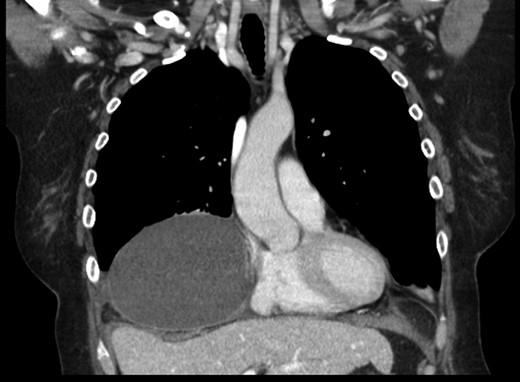

A 69-year-old female was referred to our clinic for an incidental finding of a large Morgagni hernia found on a recent CT chest scan for lung cancer screening. Patient reported occasional shortness of breath after prolonged ambulation but denied chest pain. She did have remote history of acid reflux symptoms but nothing recently. She denied issues with prematurity or issues with development as an infant, chest trauma, or MVA history. She did complain of occasional right shoulder pain but attributed this to arthritis. Denied history of heart attack, stroke, DVT, or PE. She had a 30-pack-year smoking history but quit a year prior. She was up-to-date on her colonoscopy, current within the past year. She denied hematochezia and melena, bowel habit changes or major body weight changes as well as any current abdominal pain. On examination her vitals were within normal parameters. Heart and lungs were unremarkable. Abdominal examination was soft with normal bowel sounds and nontender. Remainder of examination was unremarkable. Laboratory values included a normal CBC and BMP. A CT chest scan had demonstrated a large retroxyphoid hernia of Morgagni involving several loops of small bowel and transverse colon located in the right inferior hemithorax (Figs 1 and 2). No evidence of acute incarceration or strangulation were noted. A detailed discussion was undertaken with the patient regarding her hernia and she was consented for a laparoscopic repair with mesh.

Preoperative CT scan of chest demonstrating the wide retroxyphoid defect in the diaphragm with herniated small bowel and colon into the right inferior hemithorax.